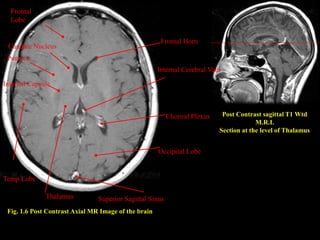

Fig. 1.6 Post Contrast Axial MR Image of the brain

Post Contrast sagittal T1 Wtd

M.R.I.

Section at the level of Thalamus

Superior Sagittal Sinus

Occipital Lobe

Choroid Plexus

. Internal Cerebral Vein

Frontal Horn

Thalamus

Temp Lobe

Internal Capsule

. Putamen

Caudate Nucleus

Frontal

Lobe

Fig. 1.6 PostContrast Axial MR Image of the brain Post Contrast sagittal T1 Wtd M.R.I. Section at the level of Thalamus Superior Sagittal Sinus Occipital Lobe Choroid Plexus . Internal Cerebral Vein Frontal Horn Thalamus Temp Lobe Internal Capsule . Putamen Caudate Nucleus Frontal Lobe

• 42.